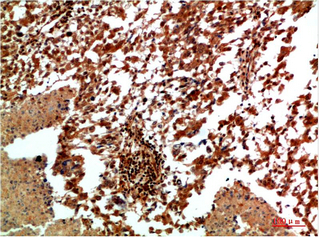

IHC (Immunohiostchemistry)

(Immunochemical staining of human MAPK9 in human lung cancer with rabbit polyclonal antibody (1:1000, formalin-fixed paraffin embedded sections).)